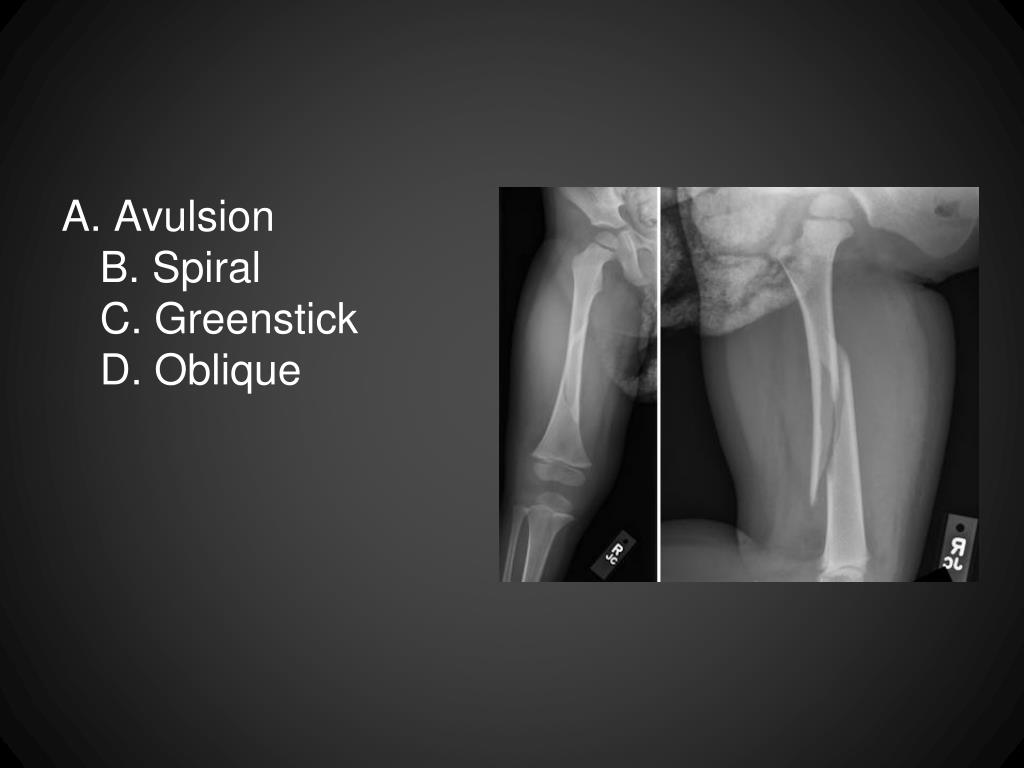

22. A. AvulsionB. SpiralC. GreenstickD. Oblique

23. Segmental Fracture